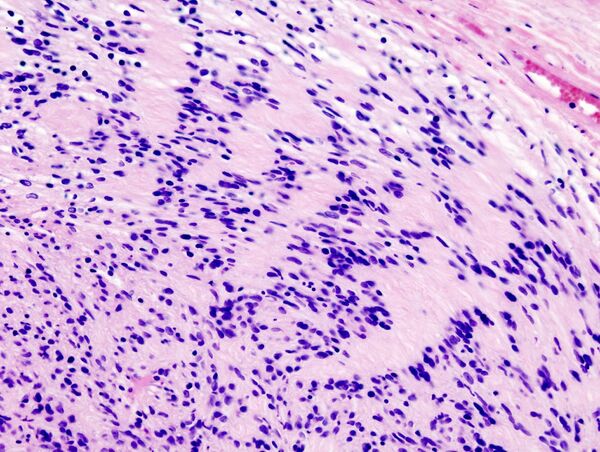

Близким термином к розетке является палисад. Палисады обычно более протяжены, образуют своеобразный «забор» вокруг гнезда опухолевых клеток. Встречается в нейральных опухолях таких как шванома[8] или амелобластома. Также палисады можно увидеть в узловом варианте базально-клеточной карциномы.[9][10]

Псевдопалисады это зоны повышенной клеточности, которые окружают очаг некроза опухолевой ткани. Это часто свидетельствует о высокой степени злокачественности опухоли.[8] Часто встречается в глиобластомах.